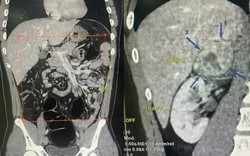

• "Bác sĩ ơi cứu em, nhưng... cho em về ăn Tết xong mổ được không": Lời cầu khẩn khiến bác sĩ khoa Thận-Tiết niệu và Nam học lặng người trước thềm năm mới

"Bác sĩ ơi cứu em, nhưng... cho em về ăn Tết xong mổ được không": Lời cầu khẩn khiến bác sĩ khoa Thận-Tiết niệu và Nam học lặng người trước thềm năm mới

Sức khỏe -

Các bác sĩ cũng nhấn mạnh, người dân không nên trì hoãn điều trị vì bất kỳ lý do nào, kể cả công việc hay chi phí, bởi khi thận đã bị tổn thương nặng, việc điều trị sẽ phức tạp và tốn kém hơn rất nhiều.